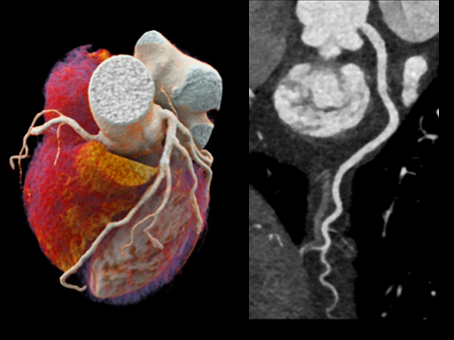

■심장 검사에 효율적인 지능형 프로세스

*ZeeFree Technology : 우수한 심장영상을 제공할 수 있는 심장 재구성 기능으로, 환자의 호흡이나 움직임으로 인해 발생하는 상황에서도 정교한 이미지를 구현합니다. 환자의 심박수에 따라 별도의 이미지 스텍을 재구성한 후, 이웃하는 이미지 스택 간의 Raw데이터를 이용하여 위상학적 재구성을 통해 우수한 품질의 심장 이미지를 제공합니다.

다음과 같은 검사가 가능합니다.

* 이해를 돕기 위한 이미지이며, 실제 촬영 시 이와 상이할 수 있습니다.